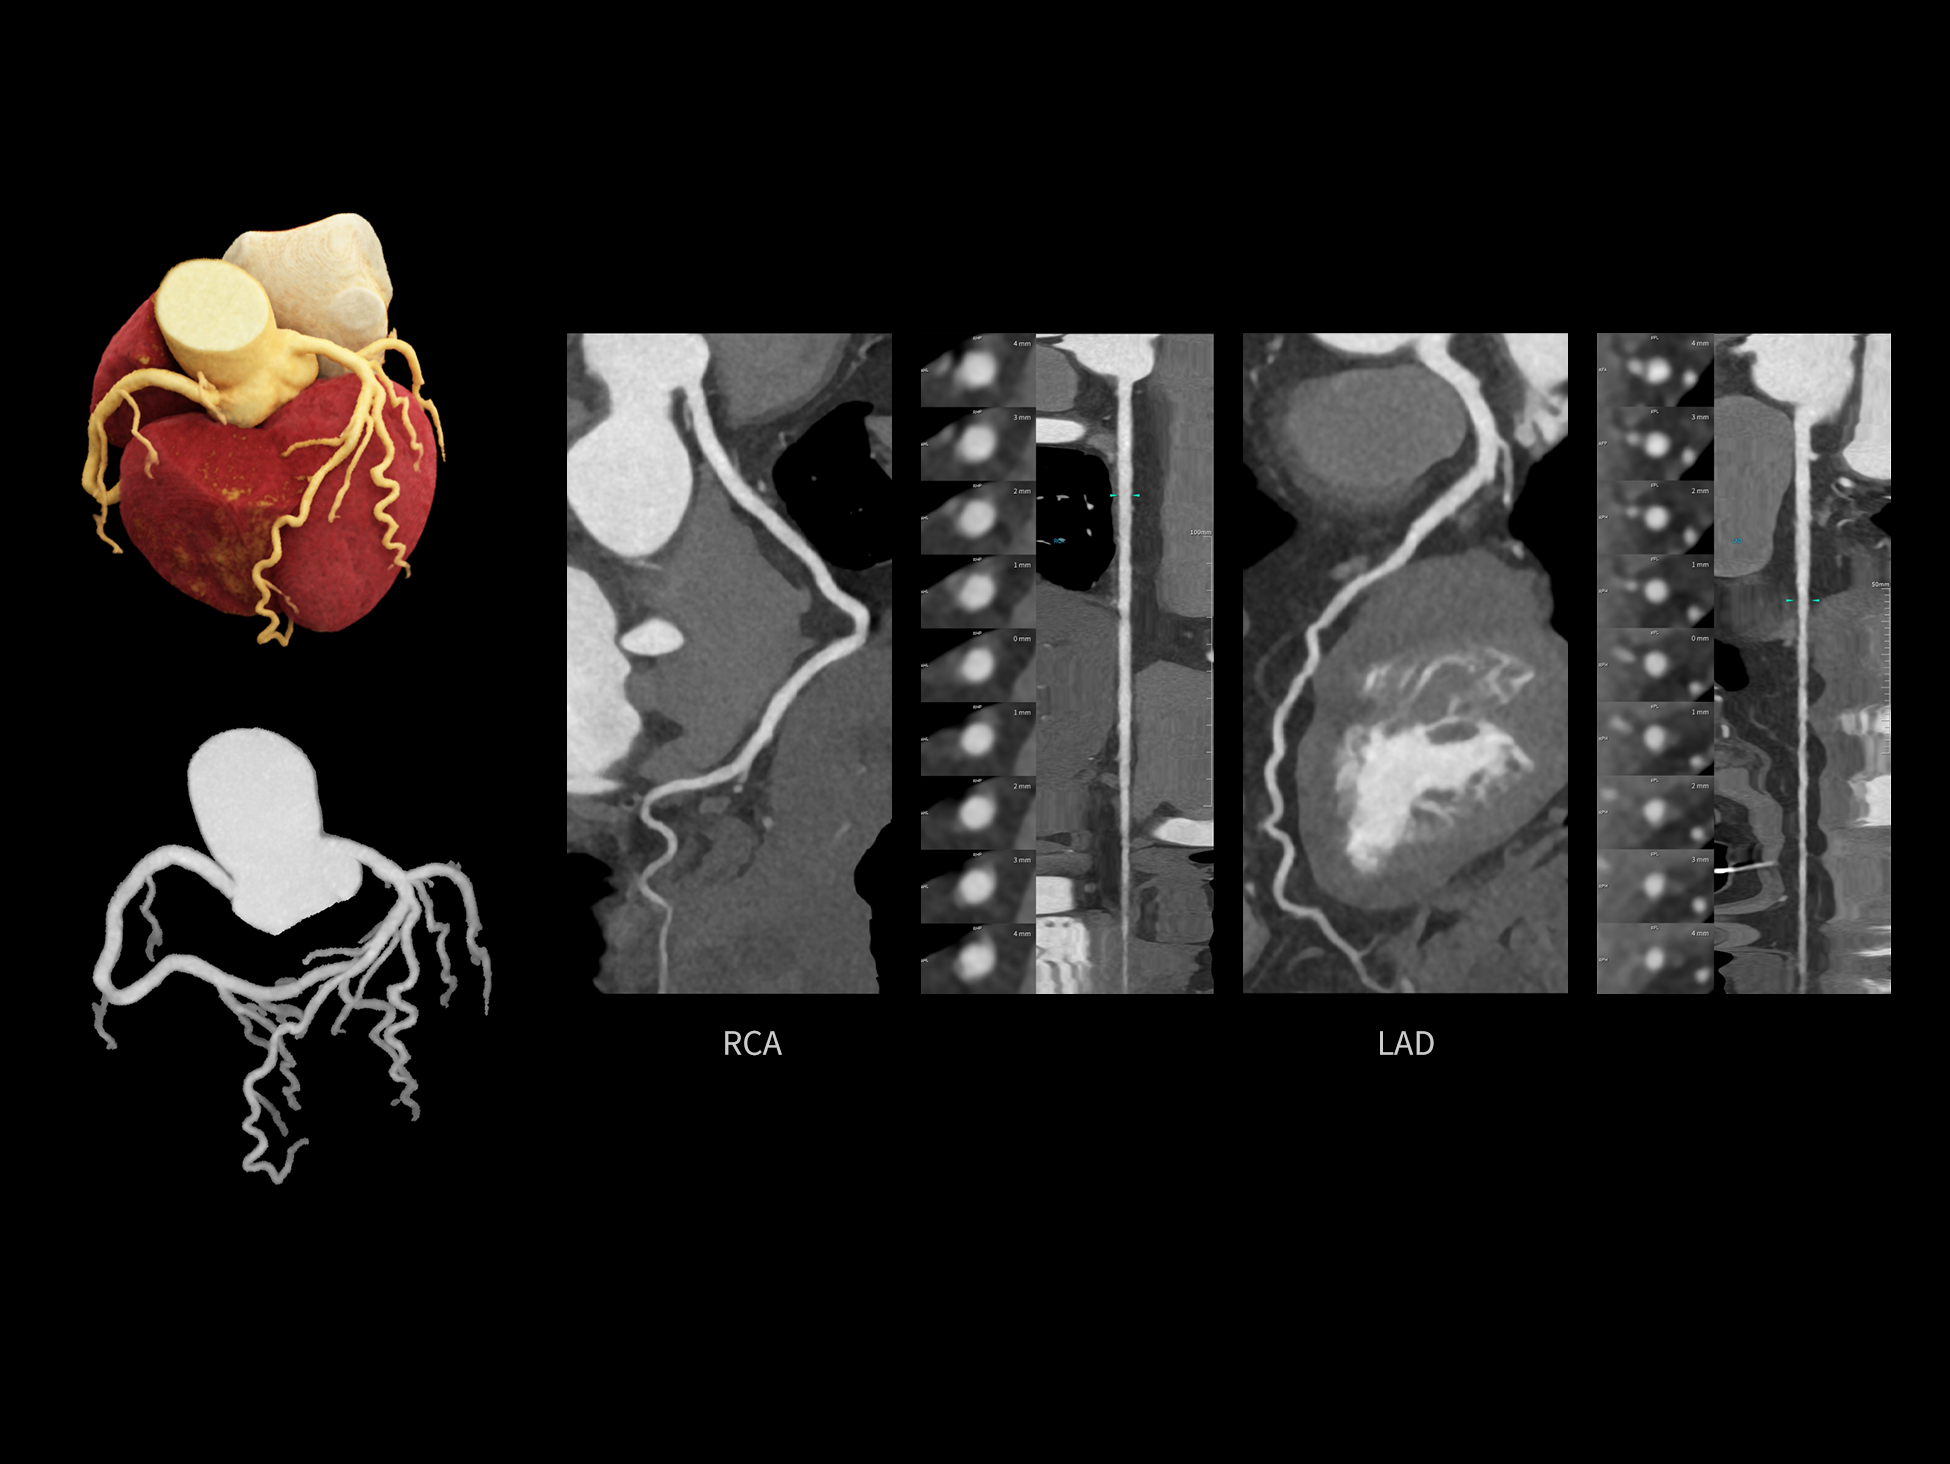

全时心脏

uCT SiriuX® 挑战心脏成像时间分辨率的极限,精准捕捉心脏全周期的动态变化。无论静态解剖形态,还是动态功能表现,都能清晰呈现,让心脏不再是“定格”的器官,而成为可视的生命律动。

突破全心时间分辨率极限

CardioCapture 2.0 通过“识别–追踪–建模–校正”的完整流程,精准分割心脏结构,动态追踪运动轨迹,并构建多时相运动场,最终实现冠脉、瓣膜、心肌及心室结构的同步校正,清晰洞见每一次心跳细微变化,真正将心脏动态掌握于毫秒之间。

CardioCapture 2.0 在目标时相前后重建多时相影像,通过深度学习网络精准提取冠脉中心线,进而建立时相间运动模型,实现对冠脉分段图像的精准运动校正。

CardioCapture 2.0 可对心肌、瓣膜及心室等结构进行同步运动校正。基于深度学习的心脏精细分割,实现了更完整的心脏全局信息提取,能有效抑制全心运动伪影,显著提升心脏细节的清晰度与诊断可靠性。

8ms 全心等效时间分辨率

冠脉运动校正

全心结构运动校正

心脏成像,自由掌控

uCT SiriuX® 以 8ms 全心等效时间分辨率与16cm宽体覆盖,突破传统心脏成像局限,完整呈现搏动中的心脏结构与动态功能;配合无心电门控扫描与智能化工作流,更使心脏检查摆脱心率、配合度与操作复杂度的束缚,实现真正自由从容的成像体验,为临床功能评估提供更深层依据。